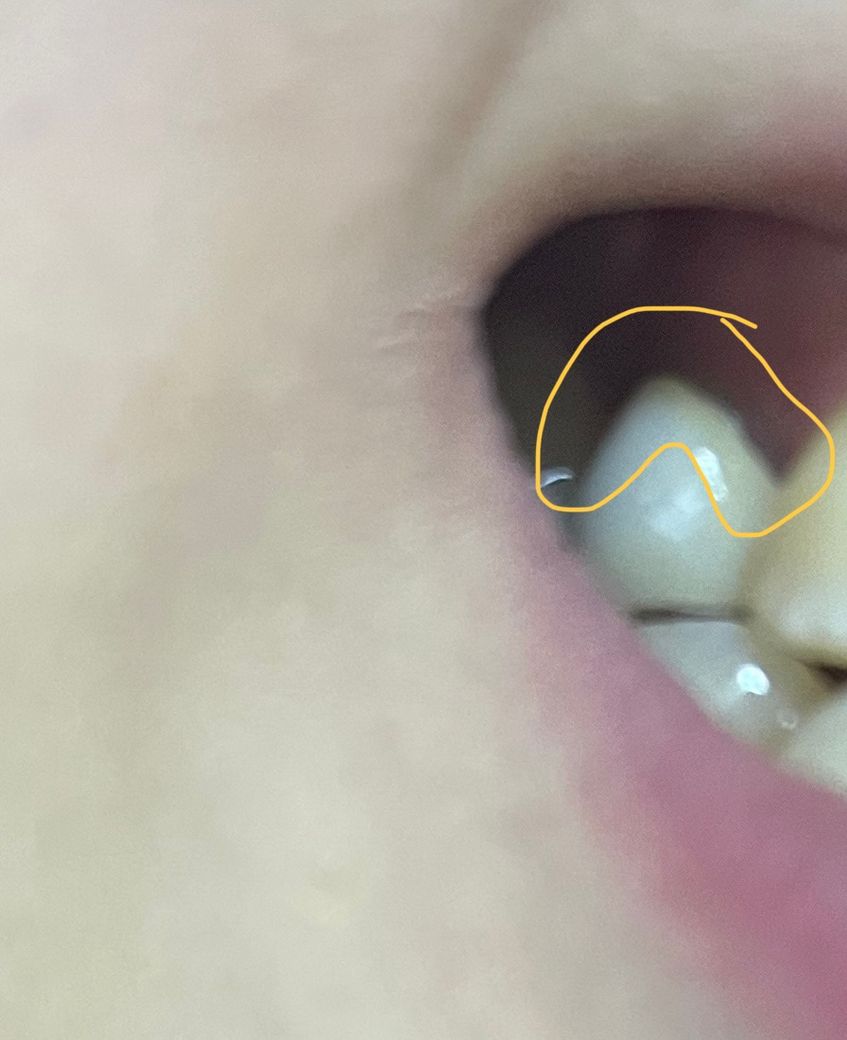

치아와 잇몸 사이에 검은선이 생겼는데 해당 부분 통증이 있는 것 같기도합니다. 어떤 질환이죠?

아래 사진과 같이 해당 치아만 검은 선이 생겼습니다ㅠㅠ

치실로 보니 잇몸이 아닌 치아 쪽에 생긴 검은색 같아요ㅠ

검은선이 아니라 보철물이 오래 되다 보니 잇몸이 내려가서 잇몸라인이 보여서 그러는겁니다. 크게 문제가 잇는건 아니니 너무 걱정하지마세요.

보철물 한 치아 인 몸에 검은색이 보인다면 보철물에 충치가 생겼을 수 있습니다.

1) 해당 치아가 이전에 씌우는 크라운 치료를 받은 것이라면 아마도 크라운을 겉부분은 치아색 나는 도자기, 안쪽은 메탈인 PFM으로 제작한 것 같습니다. 이 크라운은 처음보다 나중에 잇몸이 점차 낮아지는 과정에서 안쪽 메탈이 드러나 검게 색이 비치기도 합니다.

2) 치료받은 치아가 아니라 자연치이고 주변 잇몸색이 변한 것이라면 잇몸질환과 관련되어 잇몸색이 변했을 가능성이 있고 이는 잇몸 주의 혈관의 혈액순환과도 연관됩니다.

치아쪽에 검은 선이 생긴 경우 충치의 가능성이 있기에 빠른시일내에 치과에 방문하여 상태를 확인하고 조치를 받길 권합니다.